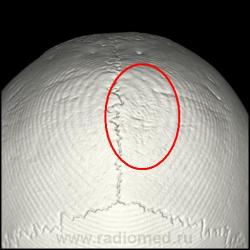

Здравствуйте. Сегодня на дежурстве попросили взять мальчика 13лет, который лежит в гемо по поводу острого лейкоза. Направили посмотреть голову с диагнозов опухолевидное образование темени. Сделал и мягкотканную и костную реконструкцию... Что писать? Немного эрозирована кость. Как описать данную картину грамотно и чему это может соответствовать?

Мой лучший интернетный друг доктор Марио (это тогда, когда мы были друзьями) предложил, в далёкие времена, создать набор по заболеваниям крови, в частности по талассемии, когда на теменных костях визуализируется "спикулёзность", правда, в Вашем случае "эрозивность"?

небольшая эрозивность и что-то мягкотканное...

Очагово-деструктивные изменения с образованием опухолевого узла (лейкемическая инфильтрация?). Биопсия. Болезненно ли? Трубчатые кости не имеют подобных изменений?

Напишу как вариант: периостоз с лейкемической инфильтрацией... Заключение сейчас отдавать уже. Трубчатые кости не снимали...